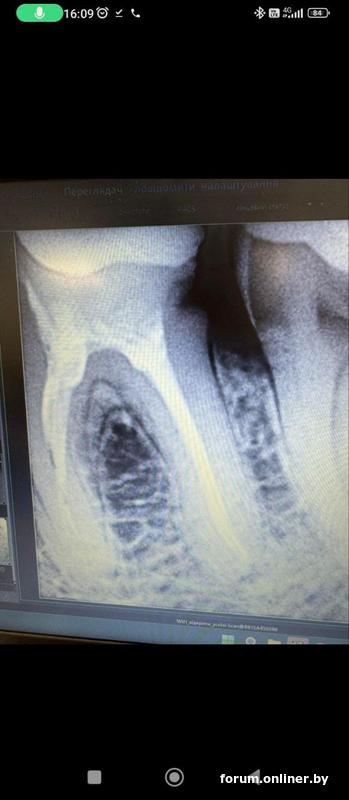

Вот это фото из клиники, которое прислали по запросу, не ясно какое до перепломбировки, какое после. Вот так и выслали, как фото с компьютера. Может будет полезно. Но первое с потемнением более свежее, а это старше где то сразу после лечения или в процессе или до, врач не уточнил и дат на фото нет.